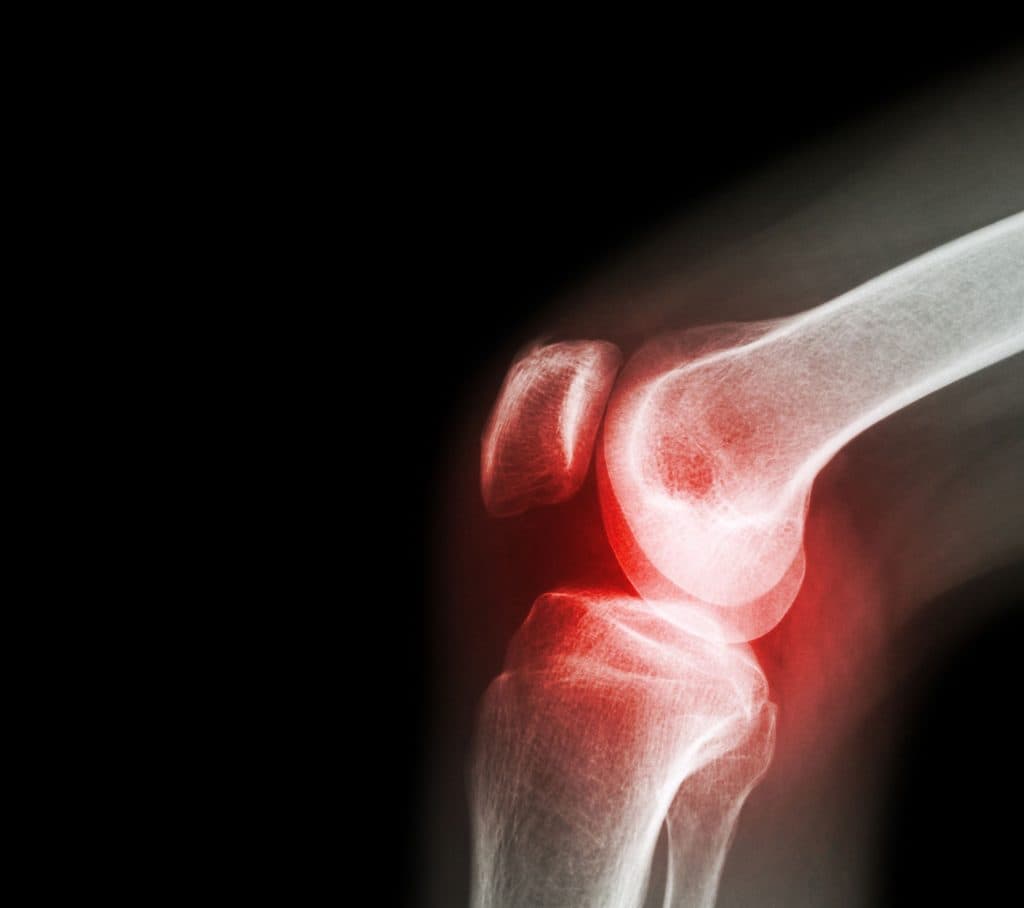

Arthrose oder Gelenkverschleiß ist eine sehr häufige degenerative Gelenkerkrankung, die jedes Gelenk betreffen kann. Am häufigsten sind die Gelenke betroffen, die das meiste Gewicht tragen, also Knie, Hüften und Wirbelsäule , oder jene, die im Alltag besonders stark beansprucht werden, etwa die Gelenke von Händen und Fingern. Arthrose kann auch eine Entzündung und Schmerzen verursachen; diese entzündliche Form wird als Osteoarthritis bezeichnet. Am häufigsten klagen Betroffene über Knieschmerzen. In den meisten Ländern werden die Begriffe Arthrose (Osteoarthrose) und Osteoarthritis klar unterschieden; im englischsprachigen Raum kommt es jedoch häufig zu Verwechslungen, selbst wenn keine Entzündung vorliegt.

Arthrose entsteht, wenn der Gelenkknorpel dünner wird und die Oberfläche aufraut. Dies geschieht durch dauerhafte Belastung und ist im Alter häufig. Begünstigende Faktoren sind unter anderem Geschlecht, Übergewicht und genetische Veranlagung. In einem gesunden Gelenk ist die Knochenoberfläche von glattem, gleitfähigem Knorpel bedeckt, der eine nahezu reibungslose Bewegung ermöglicht. Bei Arthrose nutzt dieser Knorpel ab, die Reibungnimmt zu und es können mit der Zeit Beschwerden entstehen. Der Körper startet dann Reparaturprozesse im Gelenk, die dessen Struktur verändern und häufig wieder eine schmerzfreie Funktion ermöglichen. Mit zunehmendem Alter haben die meisten Menschen in irgendeinem Gelenk eine Arthrose, oft ohne es zu bemerken. Tatsächlich findet man Arthrose bei mehr als 10 % der unter 40-Jährigen, bei über 40 % der über 40-Jährigen und bei 60 % der über 65-Jährigen ; weniger als die Hälfte der Betroffenen hat dabei Knieschmerzen.

Allerdings verlaufen diese Reparaturprozesse nicht immer reibungslos, und Veränderungen im Gelenk können manchmal zu Entzündungen, Knieschmerzen, Schwellungen und Bewegungsstörungen. Dies kann durch die folgenden Prozesse geschehen: